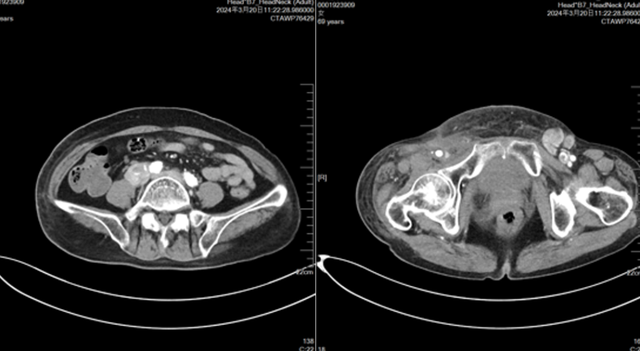

2023-11-06(PD,增大,出现新发病灶)

2023-11-06复查CT,腹腔淋巴结、左侧腹股沟区病变增大,外阴新发病灶。下肢肿胀加重。

2024-03-30(评估病情进展,下肢病灶增大,腹腔淋巴结增大,下肢肿胀加重)

左右滑动查看病例